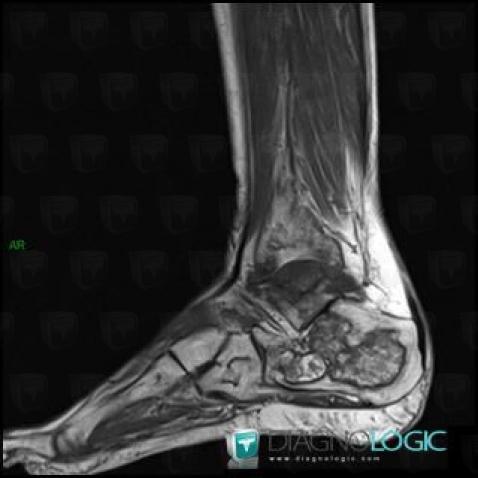

Avascular necrosis, Calcaneus, MRI

Here is the specific information in the key image above:

- Diagnosis Avascular necrosis, Location(s) Calcaneus, with gamuts Osteolytic lesion of calcaneus, T1 WI Hyperintense bone lesion, Lucent lesion in foot

Avascular necrosis, Talus, MRI

- Diagnosis Avascular necrosis, Location(s) Talus, with gamuts Lucent lesion in foot